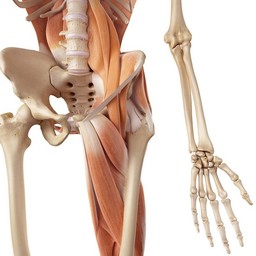

Eräitä lihaksiamme

Liikkumiskykymme perustuu lihastemme toimintaan.Ihmisessä on kymmeniä lihaksia. Esimerkiksi reidessä on monia lihaksia.

Käden suurimmat lihakset ovat hauislihas ja olkalihas. Sitä kutsutaan myös ojentajalihakseksi, sillä sen supistuminen saa käden ojentumaan.

Reisilihakset ja pohjelihakset ovat jalkojen suurimpia lihaksia.

Kuvia lihaksista